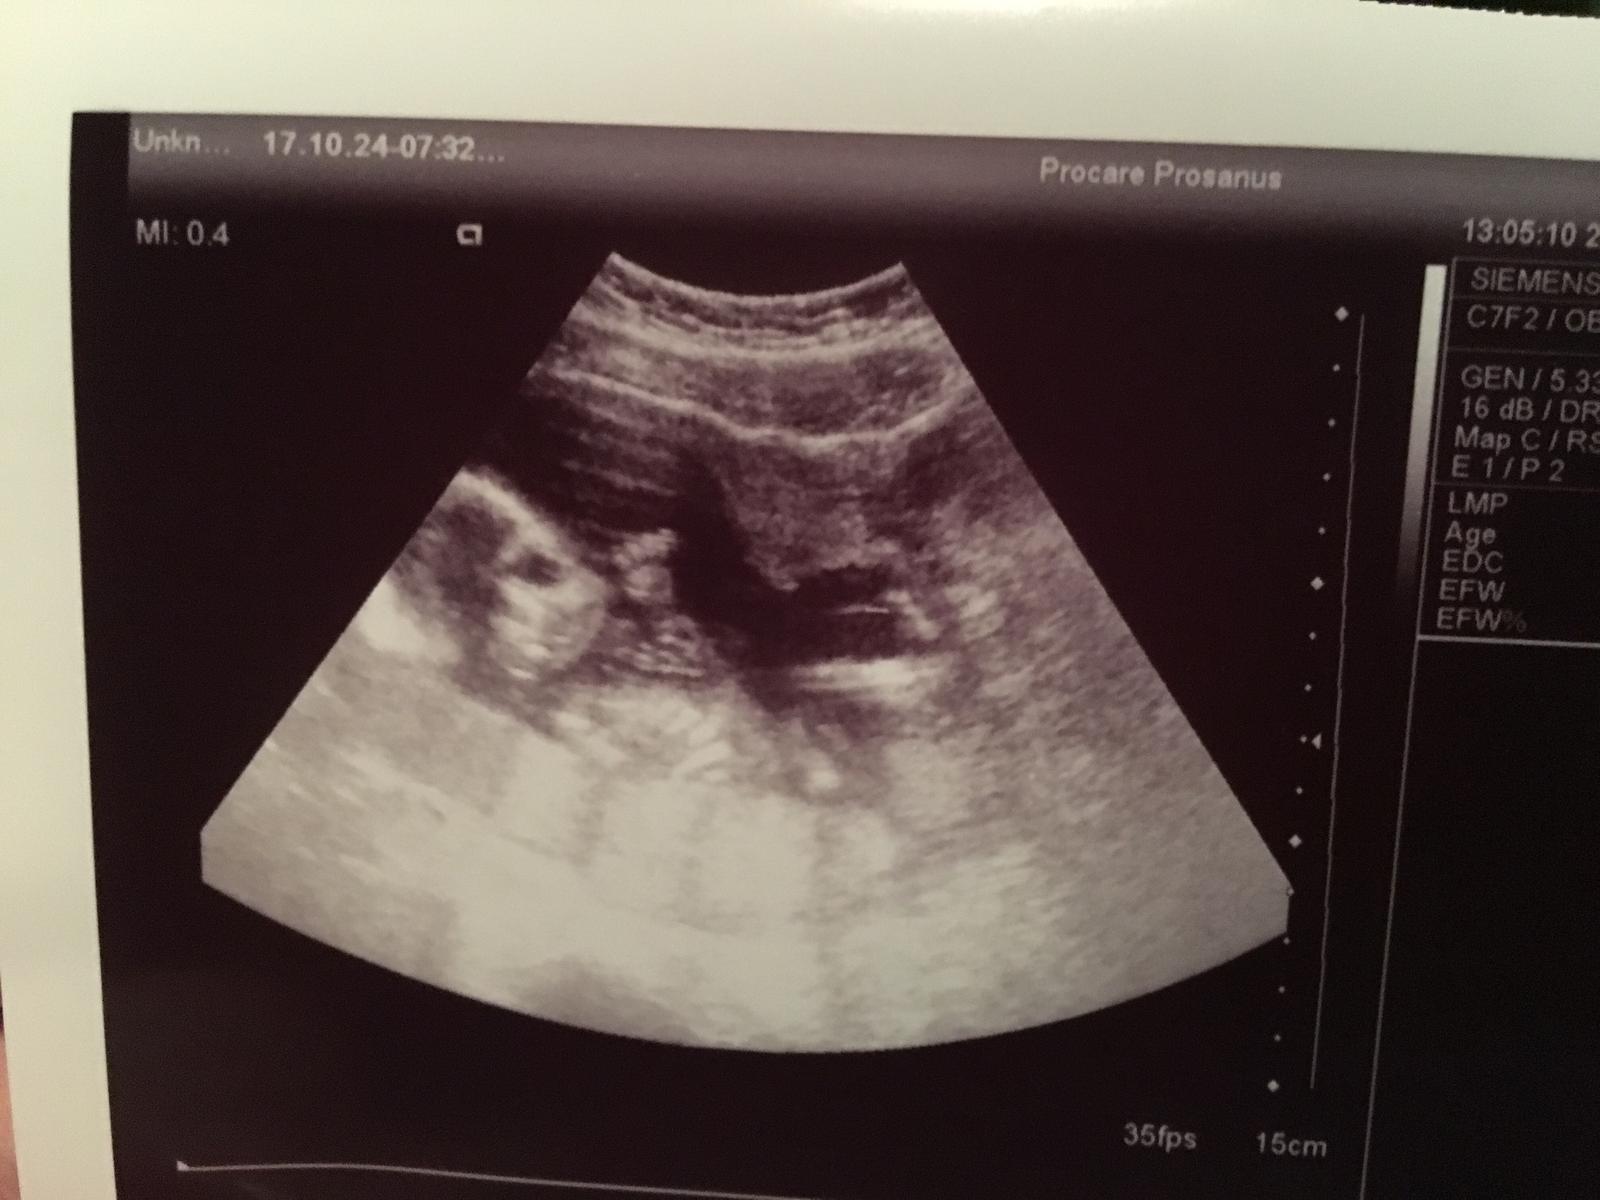

Inak ja mam taku funny mimozemstansku fotku😂Kyva nam😂